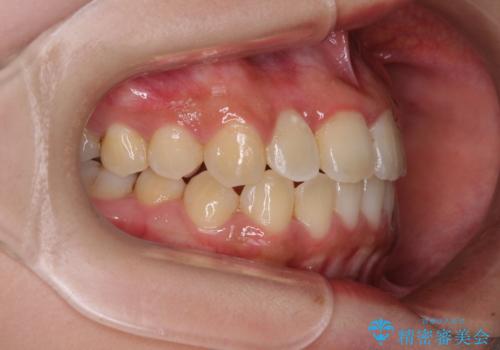

前後に重なった前歯 ワイヤー装置と急速拡大装置を併用したインビザライン矯正

- 前歯の著しい叢生とクロスバイトを気にして来院された患者様です。

叢生が強いため、一見すると抜歯矯正と判断したくなりますが、下顎臼歯が舌側に倒れていることから、上顎骨を側方拡大し、非抜歯矯正の可能性を検討することとしました。

非抜歯矯正が可能となった場合には、インビザラインにて矯正治療を行うこととしました。

急速拡大装置による上顎骨の側方拡大が思った以上にうまくいき、非抜歯での矯正が可能となりました。

内側に倒れていた下顎の臼歯は起き上がり、清掃性も大幅に改善されました。